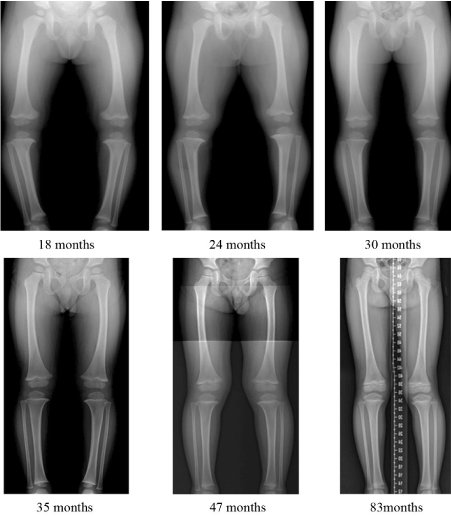

Figure 3. An 18-month-old boy had severe genu varum without definite pathology. Over time, the varus deformity decreased with aging and without treatment, neutralizing by 35 months and normalizing by 85 months. There was no definite genu valgum period

An excessive physiologic genu varum exceeding 2 SDs in young children improved spontaneously without any treatment. Despite prolongation of the genu varum period, a lack of a definite physiologic genu valgum period, and the delayed neutralization of the aTFA by 1.5 years, the aTFA in our population became similar to that previously reported for other populations: 6° valgus at age 6 years. The natural course and spontaneous resolution of excessive genu varum in our study may serve as a guideline for physicians treating excessive genu varum in young children. Because excessive physiological genu varum exceeding 2 SDs in young Korean children improved spontaneously without the need for prosthetics or orthotics, there is no need for the use of artificial limbs in this case.